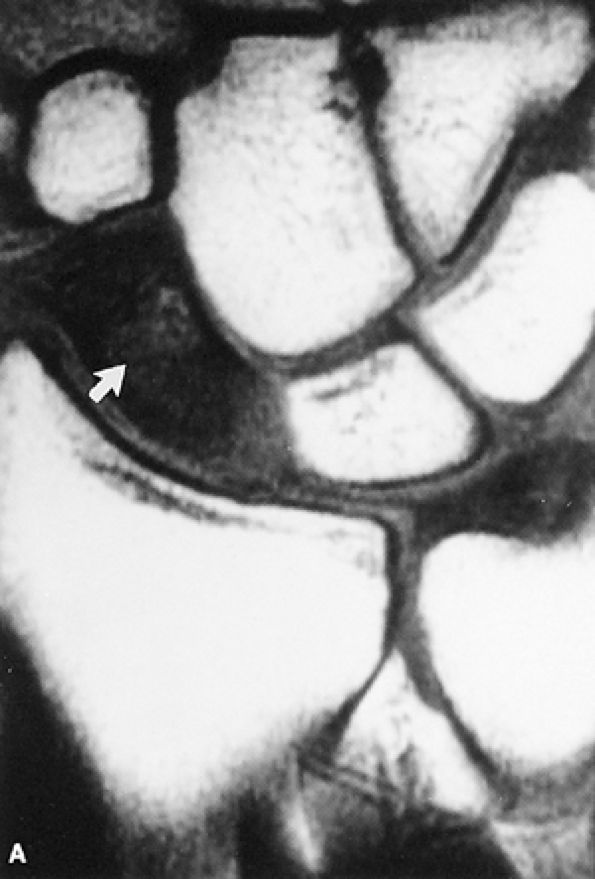

However, a fluid-filled gap interposed between the membranous scapholunate ligament and the cartilage or bones should be interpreted as a perforation or detachment. Such membranous scapholunate ligament perforations and detachments are more common with advancing age (similar to tears of the TFC central disc), and in isolation may not necessarily result in carpal instability or significant symptoms. The volar-most images demonstrate the volar scapholunate ligament, which courses obliquely and attaches to bone on either side of the ligament. Tears of the volar and radial aspects of the scapholunate ligament suspected in the coronal plane can be confirmed in the axial plane. After identifying a scapholunate ligament tear, the scapholunate interval is assessed for widening, reactive bone marrow changes on either side of the scapholunate articulation, and bony or cartilaginous avulsions at the site of tearing or detachment. In addition, in the setting of scapholunate ligament tears, associated patterns of carpal instability, such as dorsal intercalated segment instability (DISI) pattern, can be identified on corresponding sagittal images.